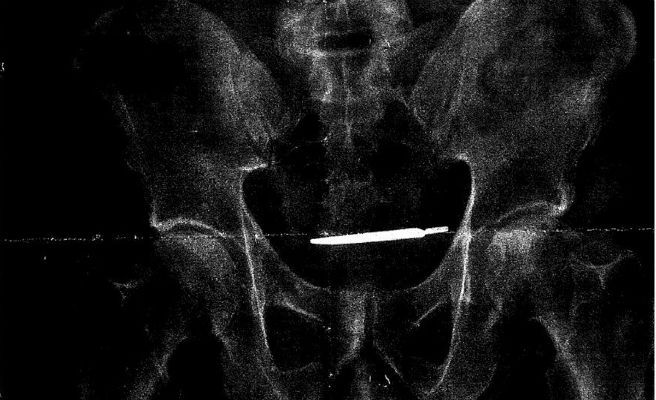

El hombre llevaba cuatro años con el bisturí dentro de su cuerpo, desde que se realizó aquella intervención, no obstante, no han descubierto el objeto hasta que el paciente ha acudido recientemente al hospital por sufrir fuertes dolores abdominales. Tras realizarle varias pruebas, una radiografía ha revelado el origen de la dolencia, ya que se podía observar el bisturí con total nitidez.